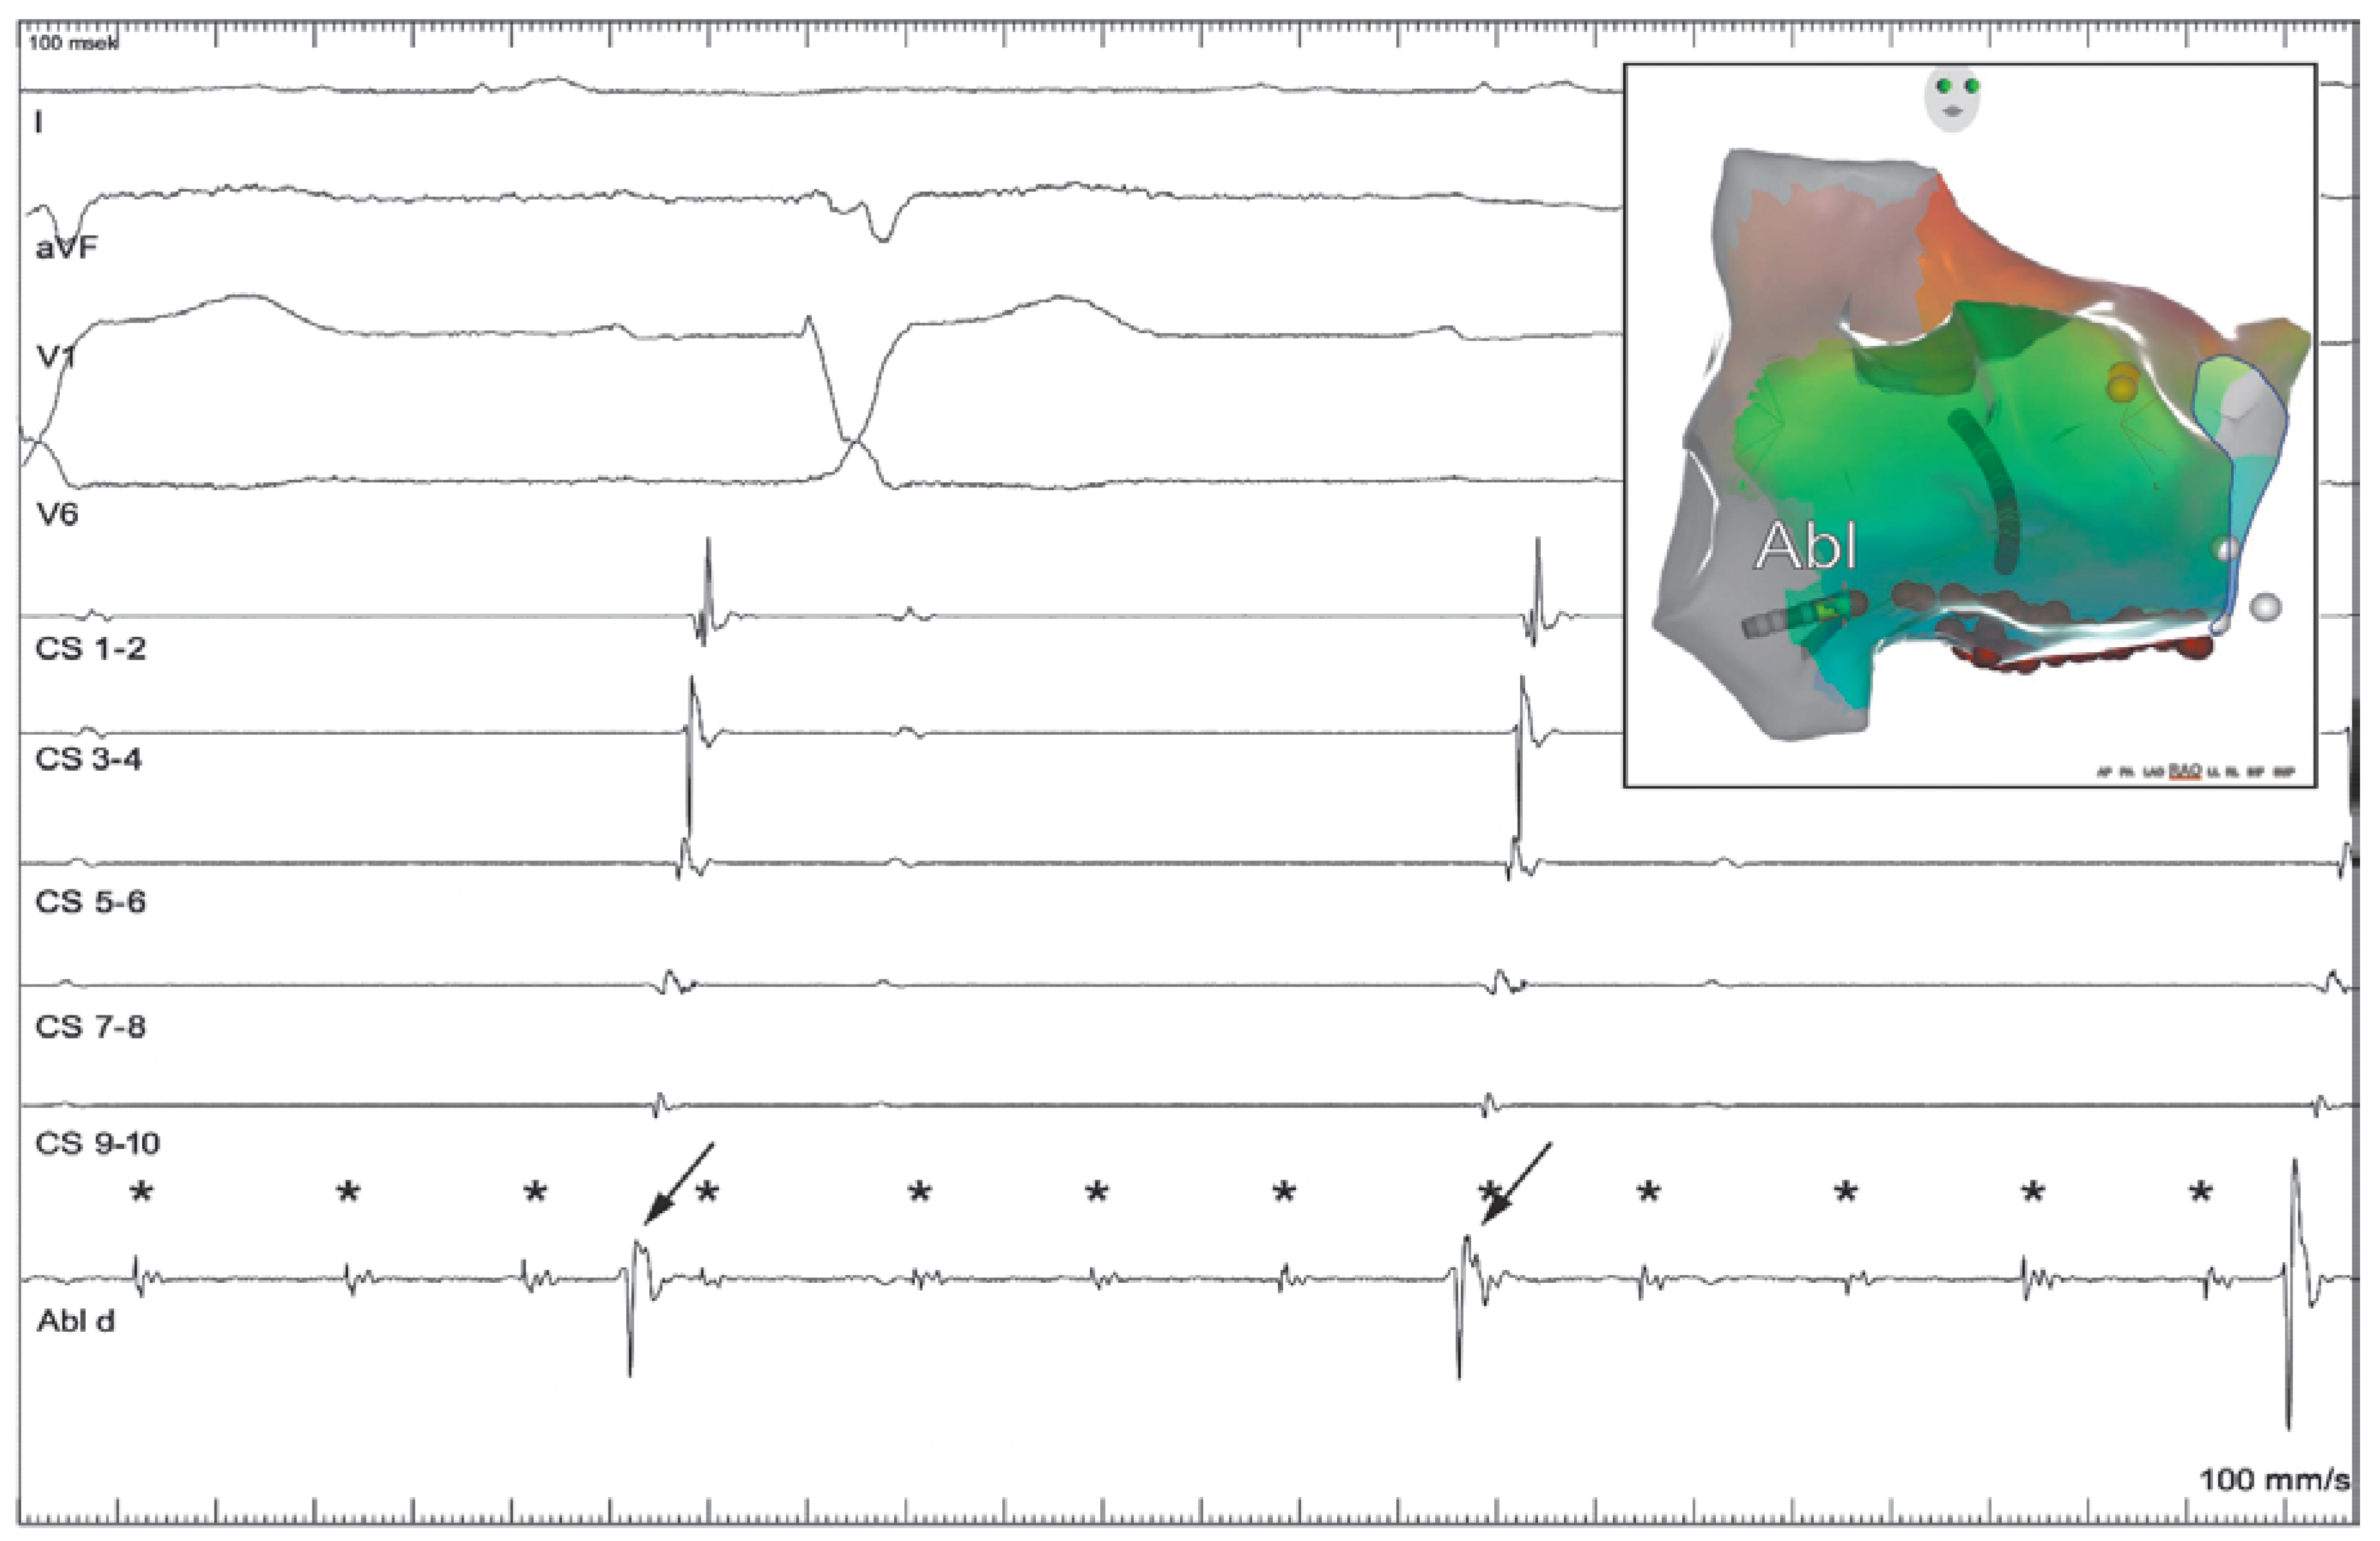

Case report